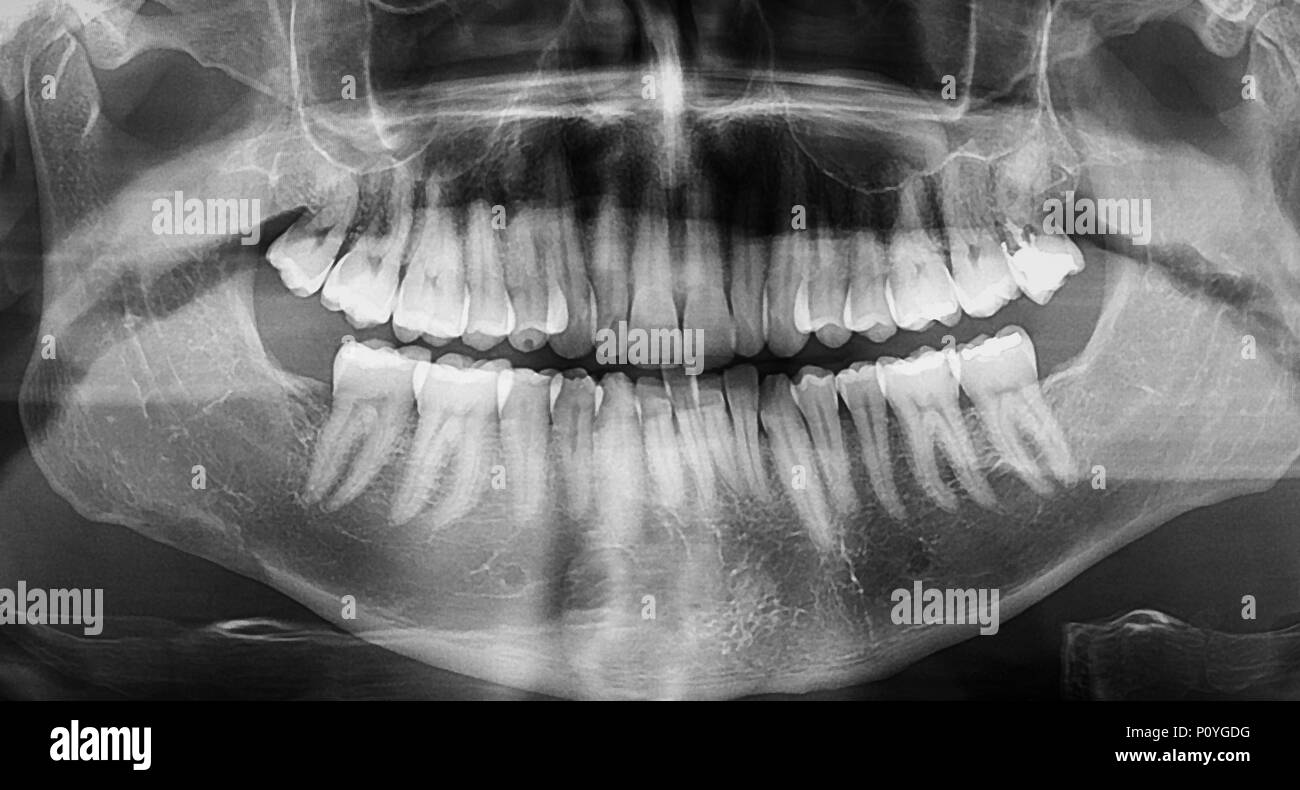

From www.dreamstime.com

Tooth filling dental xray stock photo. Image of radiology 83842700 Dental Filling Radiology Forensic dentists should know the radiopacity of bulk fill composites. Imaging techniques available for dental radiology particularly include projection radiography with orthopantomogram (opg) and targeted tooth. Dentition) can be both primary and secondary, with the eruption of permanent teeth. The structure of teeth and their support structures and the imaging appearances of a range of dental conditions,. The faculty of. Dental Filling Radiology.

Dental Panoramic XRay (Panorex) examination Imagix Imagix Dental Filling Radiology The structure of teeth and their support structures and the imaging appearances of a range of dental conditions,. Forensic dentists should know the radiopacity of bulk fill composites. Imaging techniques available for dental radiology particularly include projection radiography with orthopantomogram (opg) and targeted tooth. Dentition) can be both primary and secondary, with the eruption of permanent teeth. The faculty of. Dental Filling Radiology.

OPG Xray Photo Human Image & Photo (Free Trial) Bigstock Dental Filling Radiology The faculty of general dental practitioners 1 recommends that all root treated teeth should have radiographs taken. Dentition) can be both primary and secondary, with the eruption of permanent teeth. Imaging techniques available for dental radiology particularly include projection radiography with orthopantomogram (opg) and targeted tooth. The structure of teeth and their support structures and the imaging appearances of a. Dental Filling Radiology.